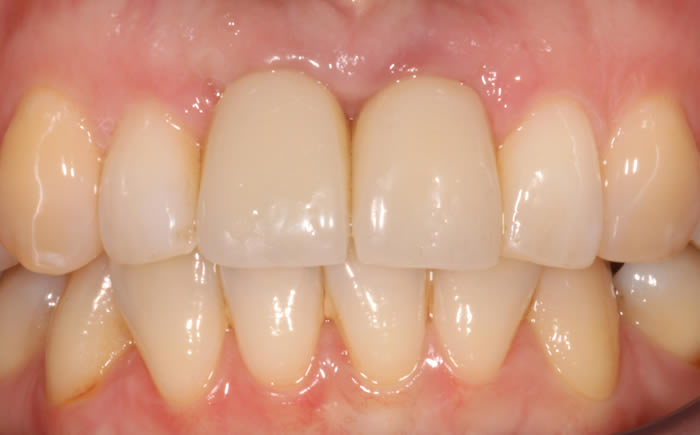

Before & After Gallery

More front teeth replaced by dental implants

Case Three (4 images)